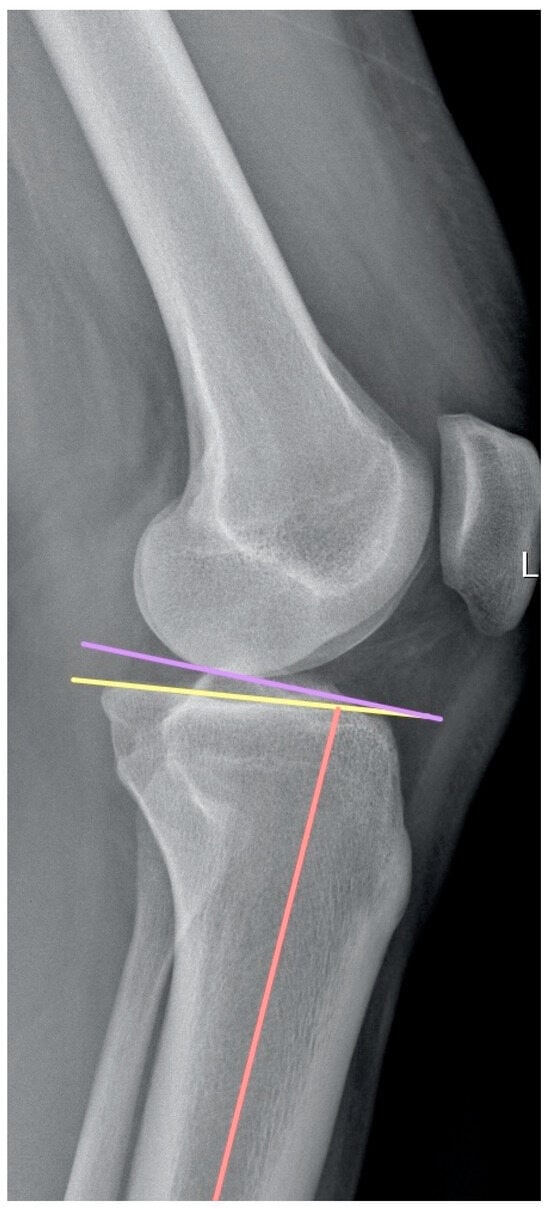

On the sagittal view of the MRI, the angle formed between the proximal and distal parts of the PCL was measured, evaluating the same sagittal cut according to the method described by Yoon et al. [9]. The angle is formed by the intersection of two lines, which follow the proximal and distal parts of the PCL (Figure 2).

Figure 2. (A,B) PCL buckling is visible on sagittal views focusing on the center of the intercondylar notch. PCL buckling angle was calculated according to the method described by Yoon et al. [9]. It is formed by the intersection of two lines which follow the proximal and distal portions of the PCL (C,D) MRI sagittal images of ramp and bucket handle lesions.